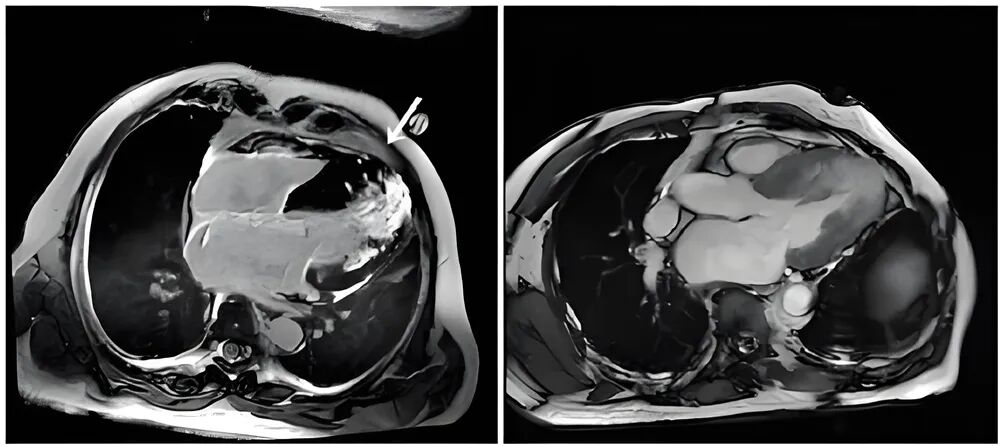

3.0T高场磁共振(MRI):具备高分辨率优势,可开展心脏磁共振等前沿项目,对心肌病变、神经损伤等精细诊断价值突出。

▲心肌梗死病灶,MRI能精准显示“土壤”级病变